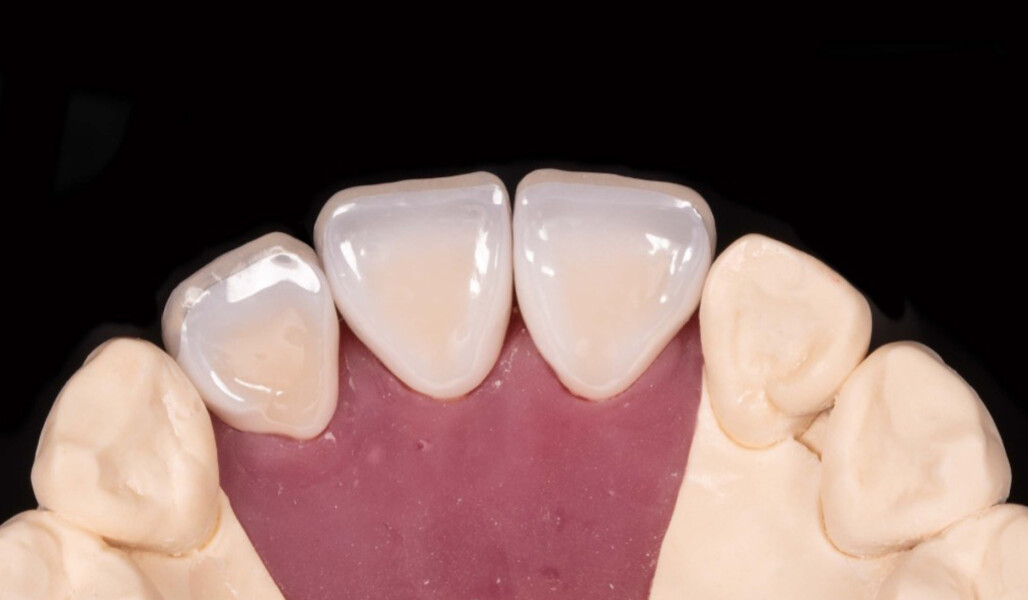

In this article, this point is demonstrated based on the case of a middle-aged female patient who presented with very unsatisfactory metal–ceramic crowns and asked for an aesthetic improvement of the situation (Fig. 1). The crowns on her maxillary central incisors and right lateral incisor clearly needed to be replaced not only for aesthetic reasons but also for functional ones. As anterior interferences were present and orthodontic treatment was not an option, the decision was made to select a ceramic material with a particularly high strength—KATANA Zirconia HT (Kuraray Noritake Dental)—and to opt for a design that would support the incisal edge with zirconia. Consequently, porcelain layering with CERABIEN ZR (Kuraray Noritake Dental) would be limited to the vestibular region (Figs. 2–11).